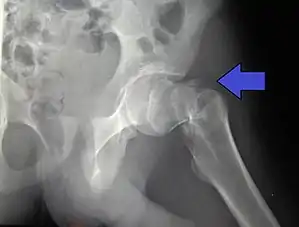

| Intertrochanteric hip fracture in a 17-year-old male | |

X-rays of the affected hip usually make the diagnosis obvious; AP (anteroposterior) and lateral views should be obtained.